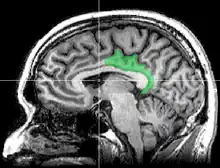

Cortex cingulaire postérieur

Le cortex cingulaire postérieur (CCP) est, dans le cerveau, une zone à l'arrière du cortex cingulaire ressemblant à une ceinture entourant le corps calleux.

- cortex cingulaire postérieur CCP, avec le même nom mais limité aux aires 23 et 31

- cortex rétrosplénial CRS, regroupant les aires 29 et 30. Il entoure directement le splenium du corps calleux.

Pour éviter les confusions, Brent A. Vogt appelle l'ensemble formé par le cortex cingulaire postérieur (CCP) et le cortex rétrosplénial (CRS), le gyrus cingulaire postérieur.